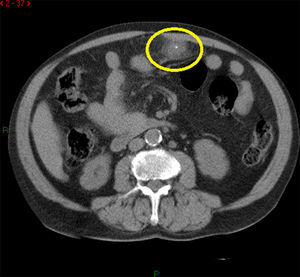

La ecografía puede indicar el diagnóstico, mostrando una masa hiperecoica ovoidea3,7,8, pero es la TAC la herramienta diagnóstica fundamental, ya que permite no solo descartar otras causas de abdomen agudo, sino realizar el diagnóstico de certeza. Se presenta como una lesión de densidad grasa mayor de 3cm, de bordes mal definidos y con imágenes lineales finas en su interior de mayor densidad, generalmente medial al colon ascendente o anterior al tranverso3,6–8.

Una entidad que radiológicamente puede simular un infarto omental es la apendicitis epiploica, pero datos en contra de esta serían el tamaño superior a 3cm y la ausencia de anillo hiperdenso en la TAC con contraste. Ambas entidades forman parte de lo que se conoce como «infarto graso focal intraabdominal», siendo su manejo similar, por lo que la diferenciación entre una afección y otra carece de relevancia clínica8,9.

Pese a la analgesia administrada, el dolor persiste, por lo cual se solicita ecografía abdominal, donde se objetiva líquido libre sin otro hallazgo patológico. Se decide realizar TAC, con la que se llega al diagnóstico definitivo de infarto omental.